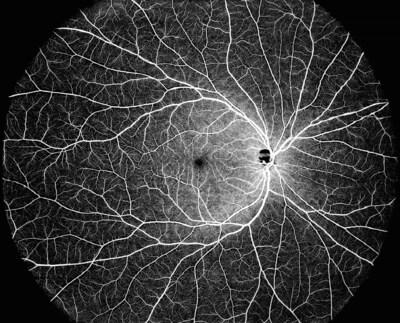

DREAM OCT может охватить сверхширокое полевое одиночное сканирование, которое обеспечивает изображение с ОКТА-изображением 130°. Сканирование DREAM OCT со сверхглубиной 12 мм обеспечивает превосходную визуализацию сосудистой оболочки и сетчатки, а также большой части стекловидного тела. Сверхглубокие возможности переднего сканирования достигают 16,2 мм (на воздухе), что позволяет сканировать весь передний сегмент от роговицы до передней части стекловидного тела только за одно сканирование. Более длинная волна обеспечивает превосходное проникновение через помутнение либо в хрусталике, либо в стекловидном теле.

Используя сверхширокую технологию развертки, технология DREAM OCT была разработана для удовлетворения потребностей специалистов по сетчатке, комплексных офтальмологов и их пациентов с высокодетализированными возможностями визуализации для улучшения ухода и результатов. В настоящее время более 160 рецензируемых статей используют результаты устройств DREAM OCT.